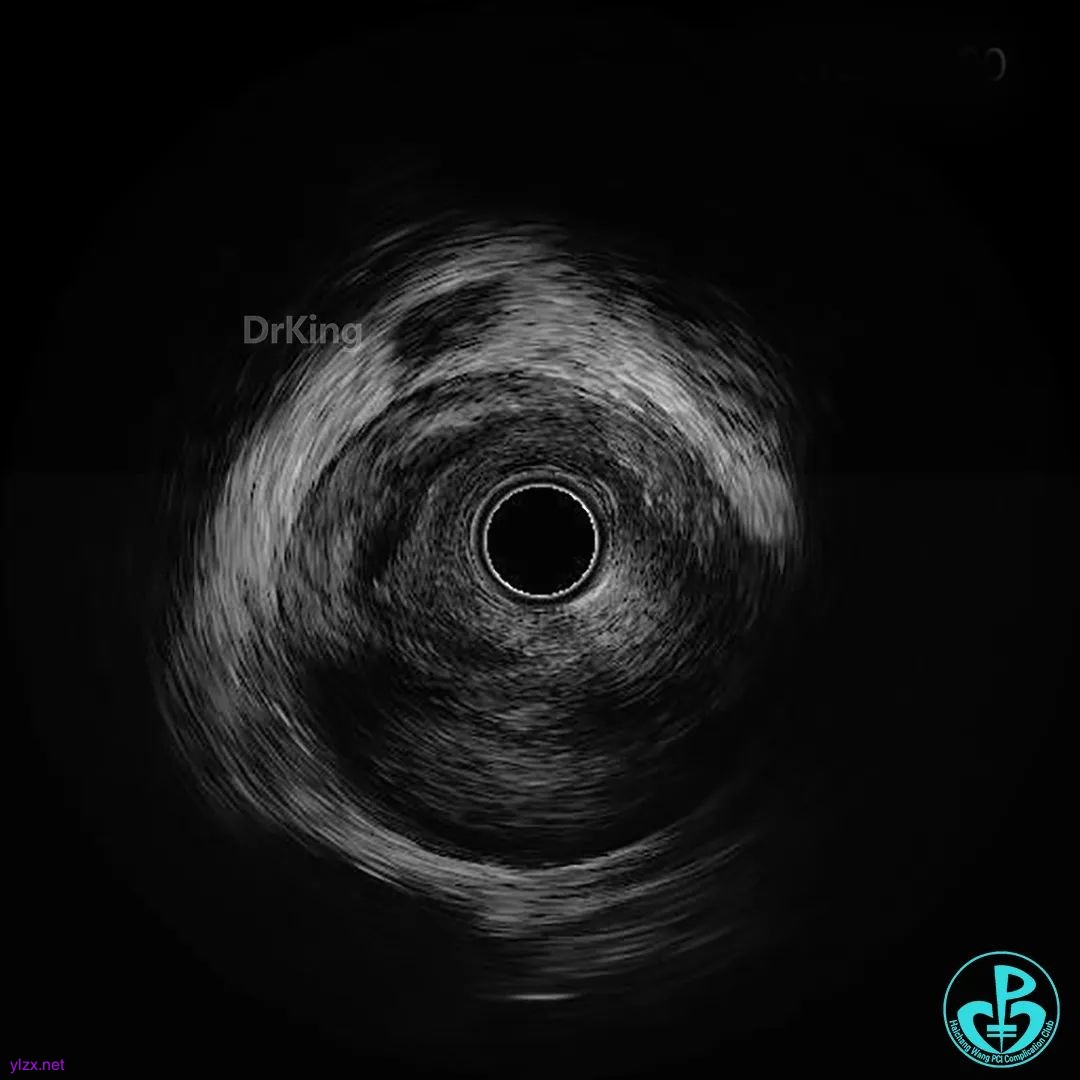

近端3.5×33mm支架至开口,中段接3.0×33mm支架。后扩张处理后远端仍然造影剂滞留。

PL近端2.5mm切割球囊扩张后,造影剂滞留改善。

远端至PL近端接2.75×33mm支架后,血流彻底恢复。

3.0×15mm及3.5×15mm球囊优化以后最后造影。

超声证实支架膨胀及贴壁良好,血肿消失,症状缓解。好惊险!